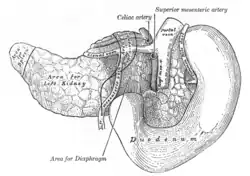

The pancreas and duodenum from behind

The pancreas and duodenum from behind -

Arteries and veins around the pancreas and spleen

Arteries and veins around the pancreas and spleen